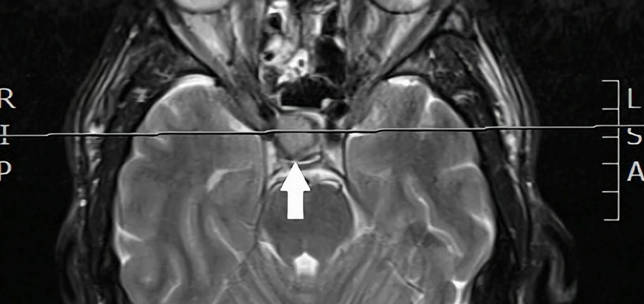

Photophobia: an unusual symptom of a pituitary macroadenoma

Kathryn O’Brien

,

Henry Z Lin

Anthony Vivian

·

2nd February 2024